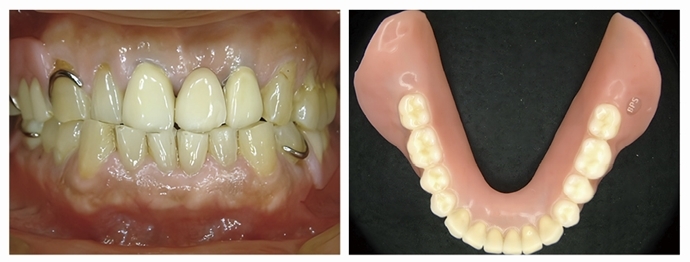

◆作法:活動式假牙有分全口式活動假牙及局部式活動假牙兩種,黃斌洋院長表示,是用金屬扣、鈎子或磁鐵鈎在健康牙齒上的補牙治療,可自行取下,不會過度修磨旁邊的牙齒,也不需要開刀。製作活動式假牙的牙材有三類,支架類多為合金材質,牙肉類多為壓克力樹脂,牙冠是複合樹脂壓鑄。

活動式假牙樣貌

活動式假牙是用金屬扣鈎在健康牙齒上。(圖/柏登牙醫診所黃斌洋院長提供)